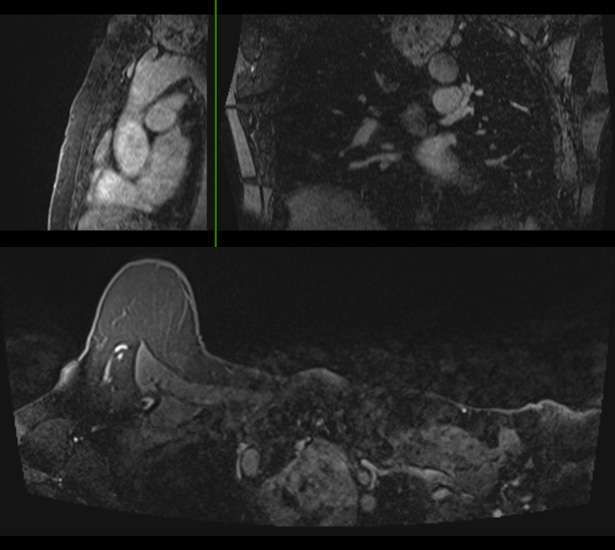

Case: Non Breast Finding Seen on Breast Imaging Figure 1

Figure 1. Cholelithiasis with mild proximal cystic ductal dilation on axial STIR imaging. Recommendation for correlation with patient's symptoms and liver function tests with consideration to right upper quadrant ultrasound versus MRCP was made.